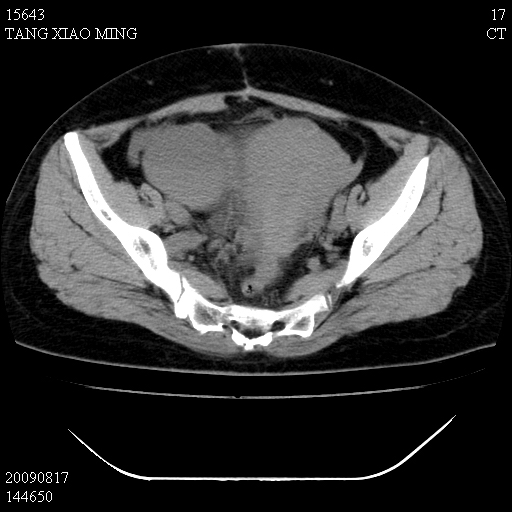

标题: CT21692:盆腔病变

女,33岁,右下腹痛2年余,既往宫外孕病史,如在我院手术,结果下周公布,

可能的诊断。1子宫内膜异位【子宫腺肌症并右卵巢巧克力囊肿】;2 右卵巢囊腺瘤。子宫肌瘤

1)考虑卵巢巧克力囊肿,不排除卵巢囊腺瘤。2)子宫肌瘤可能。

卵巢囊腺瘤,子宫肌瘤,直肠壁厚,不除外占位.